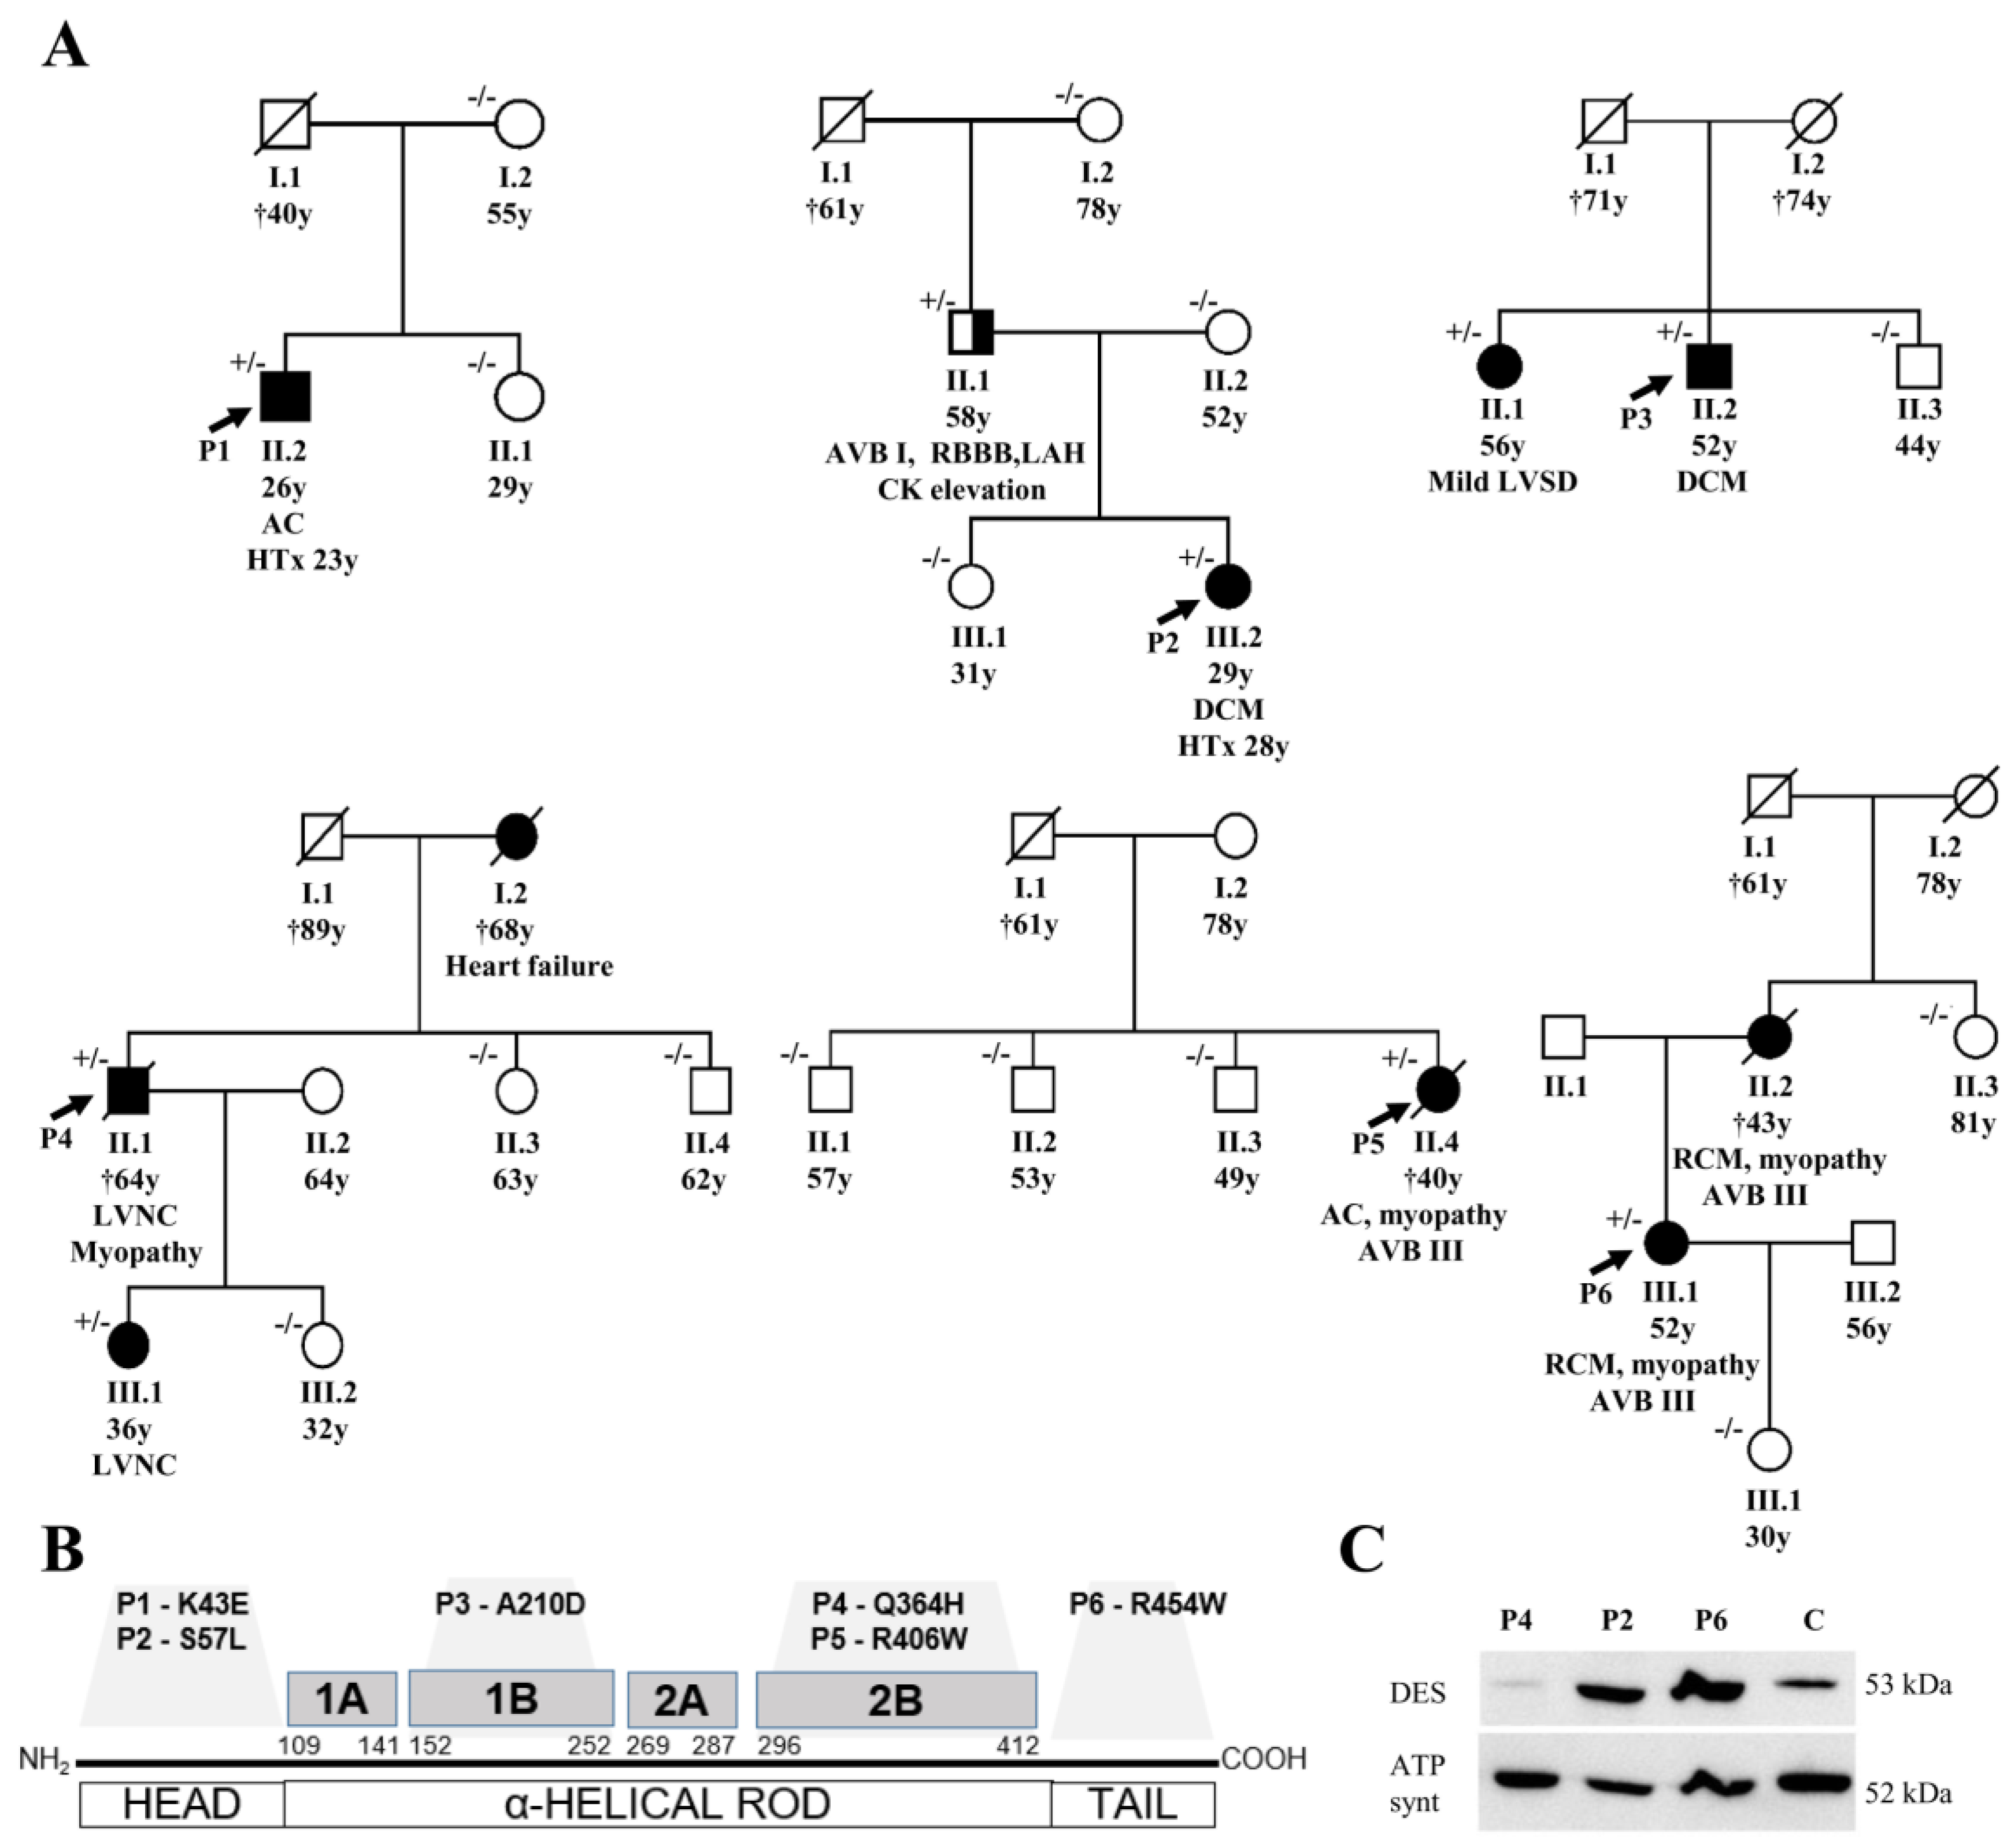

3.1. Description of DES Variants and Their Segregation in Families

3.2. Phenotypes of Desminopathy

3.4. Indications for the Pathogenicity of the Novel Desmin Variants